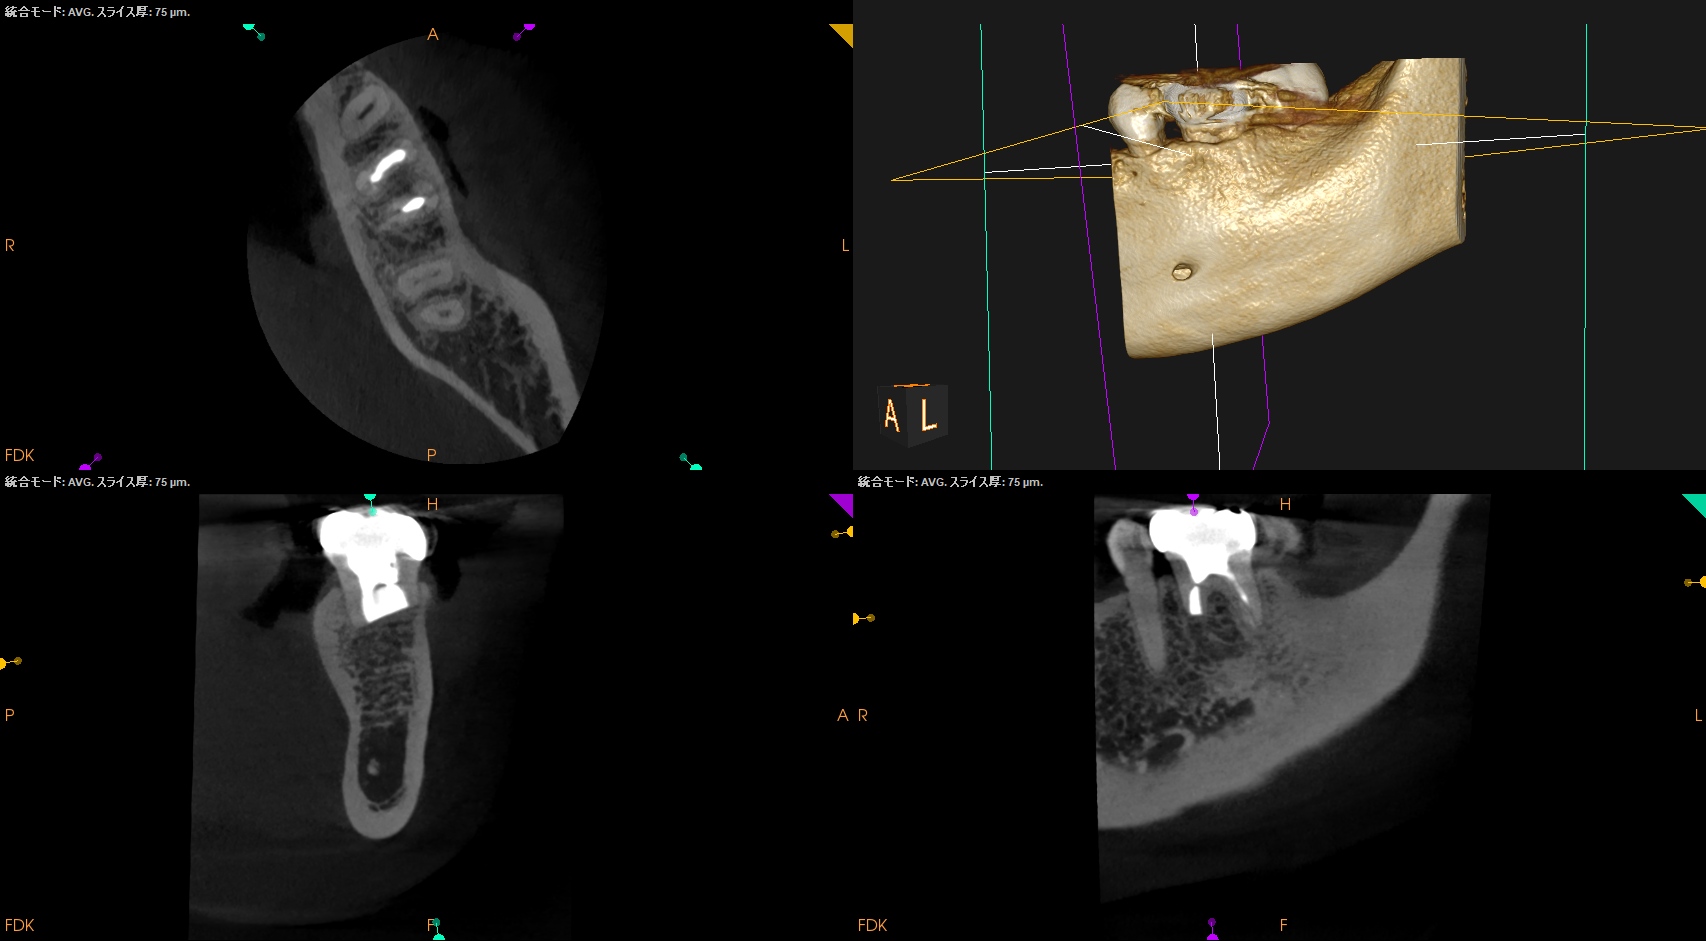

臨床症状の原因は#19の近心根の根尖病変だろう。

当該部位を2mm Osteotomyすると#19 MのApexが発見できそこを3mm切断するには頬舌径が6.2mm必要である。

当該部位をOsteotomyした。歯槽骨は2mm削合する必要がある。

Apexを3mm削除し取り除いた。

術後にPA, CBCTを撮影した。

術後の骨欠損は完治した。